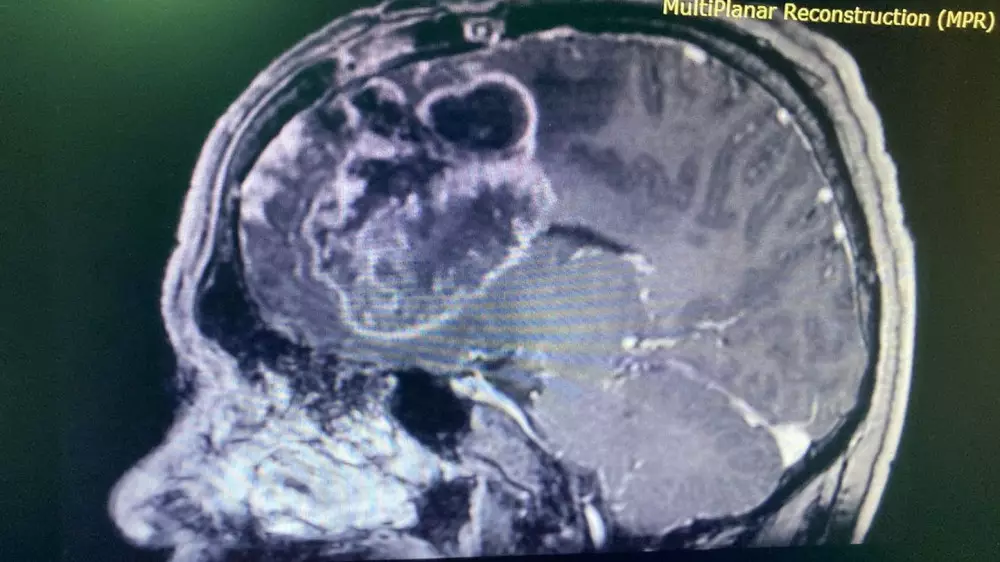

Мужчина жаловался на головные боли, головокружение, снижение зрения, снижение памяти, слабость в левых конечностях, а также на судорожные приступы. Пациенту был поставлен диагноз "гигантская глиальная опухоль правой лобной доли с прорастанием в мозолистое тело в стадии клинической декомпенсации". Размер опухоли составил семь на семь сантиметров.

Врачи отделения нейрохирургии патологии головного мозга провели шестичасовую операцию по микрохирургическому удалению глиальной опухоли с применением МРТ-трактографии и нейронавигации.

"Прицелившись к опухоли, мы аккуратно обошли двигательные зоны, а также крупные артерии. Также точность удаления опухоли зависела от координат, которые были построены заранее с помощью МРТ-трактографии – это новая методика, показывающая ход и структурные изменения проводящих путей головного мозга (тракты белого вещества), кроме этого, применялась и нейронавигационная система. Благодаря такому технологическому оснащению мы смогли не задеть вышеуказанные структуры и зоны", - рассказал лечащий врач пациента Тлеубергенов Муратбек Абдигалиевич.